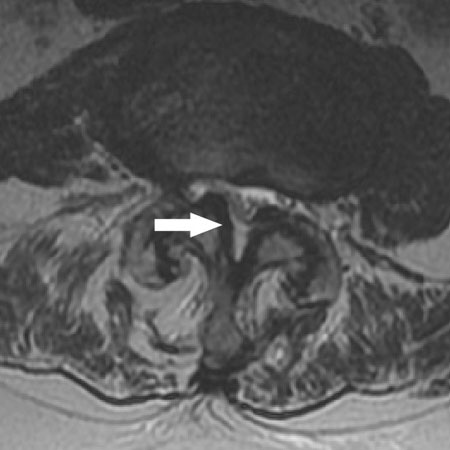

Ressonância nuclear magnética da estenose da coluna vertebral: a seta aponta para o canal vertebral com estenose moderada causada por facetas hipertróficas e ligamento amarelo

Cortesia do Dr K. Singh; usado com permissão